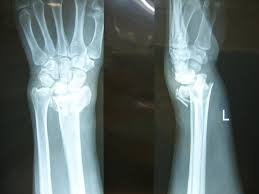

- 小伙骨折住院三天 医院做不了手术称要等到初八